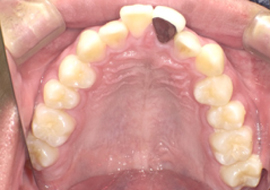

Before

| 主訴 | 上前歯のガタガタを治したい |

|---|---|

| 年齢 | --- |

| 治療期間 | 約1年 |

| 治療内容 | インビザラインiGoで上顎のみ治療。 プチ矯正では前から3番目の歯は動かせないが、 この治療では動かすことができるので、 気になる箇所を綺麗に並べることができた。 |

| 治療費 | ¥352,000(税込)+月額調整料 |

| 治療のリスク | 歯と歯の間を削ることでスペースを確保するので、 場合によっては歯が染みる症状が出ることがある。 |